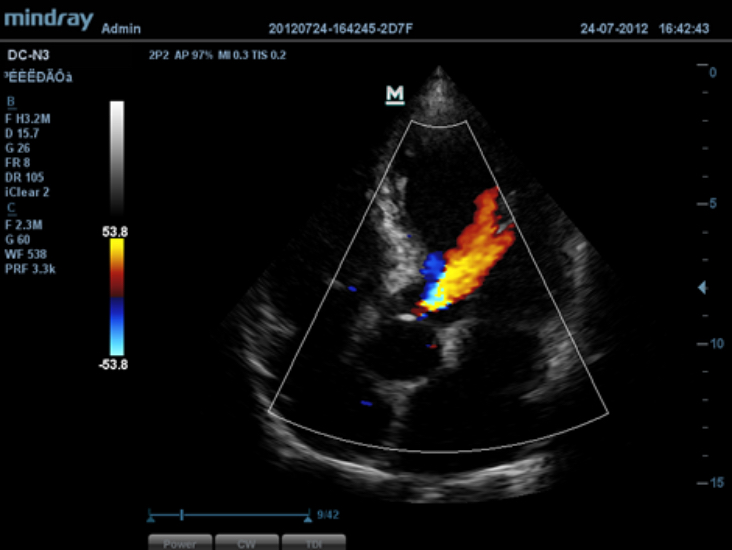

DC-N3 PRO? ??? ??? ??, ???, ???? ?? ???? ??? ?? ?????. ?? ??? DC-N3 PRO? ??? ??? ?? ??? ??? ???? ???? ??? ????? ??????. ???? ?? ???? ???? ?? ??? ???? ???? ???? ?? ? ????.

DC-N3 PRO? ??? ??? ?? ??? ??? ????? ?? ???? ???? ??? ?? ??? ??? ?? ???? ??? ?????. ?? ??? ??, ???, ??? ?? ??? ??? ??? ?????. ????? ???? ???? ????? ??? ???? ??? ?? ?? ?? ??? ??? ???? ??? ?????.